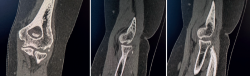

A las 12 semanas, es revisada nuevamente en consultas. A la exploración física, presenta dolor en la cara lateral del codo derecho, chasquidos a la pronación, maniobra de pivot shift positiva y bostezo doloroso en varo. Se solicitaron pruebas complementarias: unas radiografías, en las que se aprecia la lesión de Osborne-Cotterill (Figura 1), una resonancia magnética (RM) en la que se objetiva una desinserción distal del ligamento colateral lateral cubital y proximal del ligamento colateral radial, además de rotura parcial de ligamento anular, y una tomografía computarizada (TC) en la que se mide defecto osteocondral de Osborne-Cotterill en el capitellum posterior de 8 × 3 mm (Figura 2). La paciente sufrió un nuevo episodio de luxación posterior en la siguiente semana, tras una nueva caída mientras se encontraba en rehabilitación, por lo que se realizó una segunda reducción cerrada.

Figura 2. Tomografía de la paciente, cortes coronales y sagitales, en los que se aprecia un defecto óseo en el capitellum de 10 × 8 × 3.